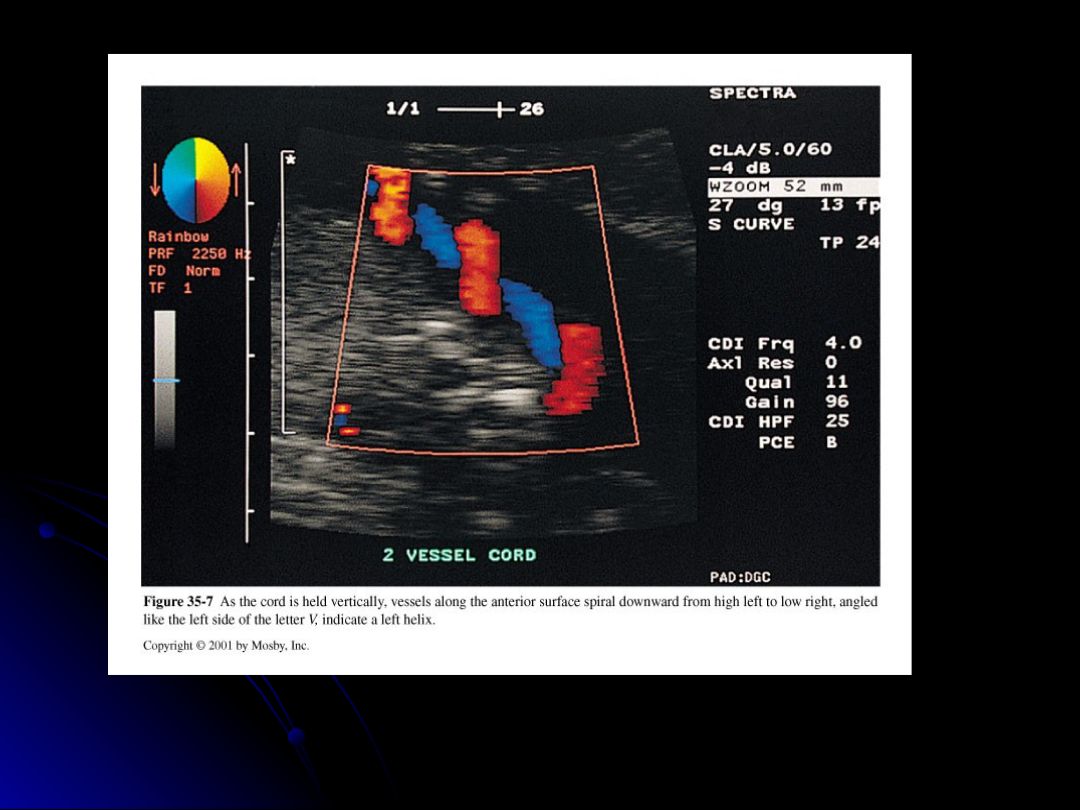

Which of the following statements about the twists of the umbilical cord are correct?

A left helix is more common than a right helix.

Twist is determined by ultrasound only.